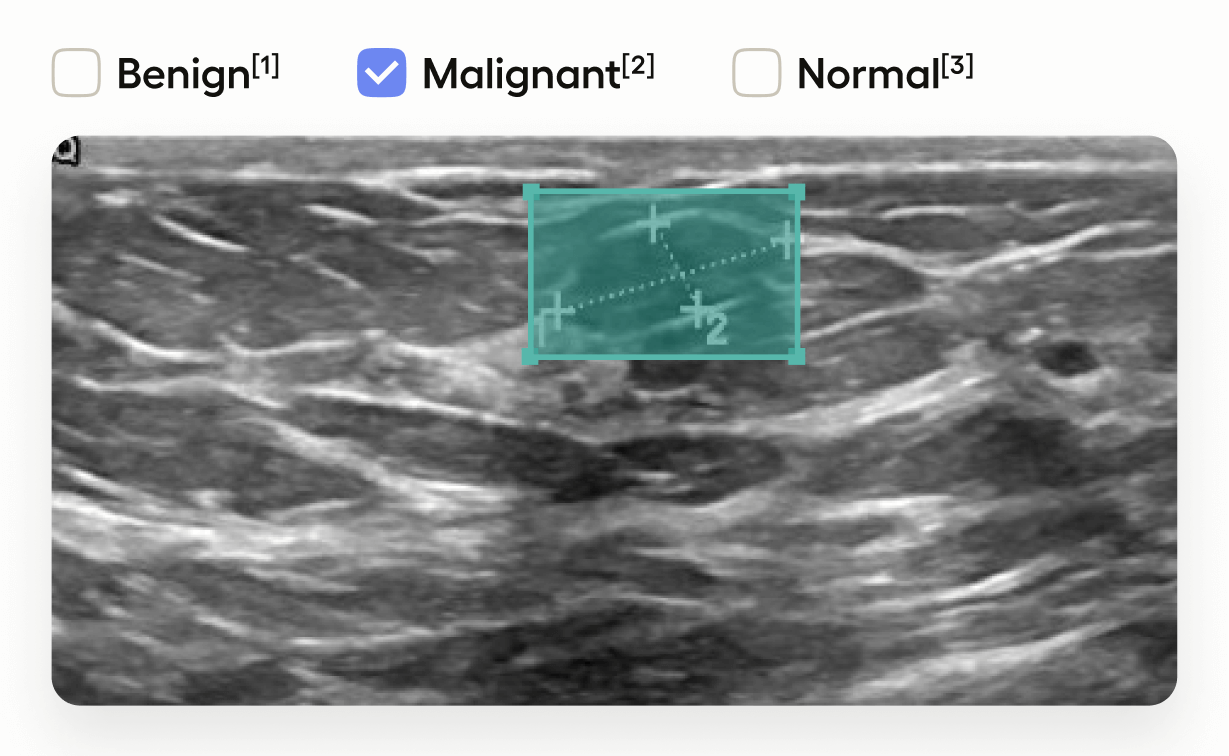

This template interface allows annotators to:

- Draw bounding boxes around areas identified as tumors in the image using the “Tumor” label.

- Classify the entire image by selecting one of “Benign”, “Malignant”, or “Normal”.

This setup is useful in medical imaging tasks where you need to localize tumors and also provide an overall assessment of the image.

This adds image-level classification choices.

applies these choices to the entire image.- Annotators can classify the image as “Benign”, “Malignant”, or “Normal”.